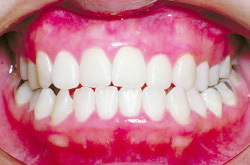

上あご・正面・下あご

before

after